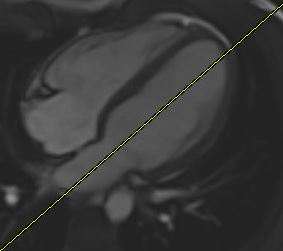

2 Chamber View